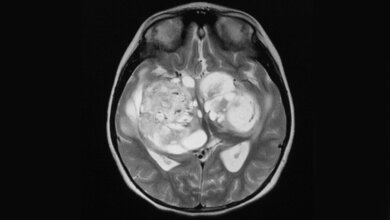

Patienten mit Glioblastom, einer besonders aggressiven Variante von Hirntumoren, entwickeln oft sogenannte Rezidive – das bedeutet, der Tumor kehrt trotz der Behandlung wieder. Um dies zu verhindern oder zumindest hinauszuzögern, werden die Patienten nach ihrer Tumoroperation intensiv mit einer Kombination aus Chemo- und Strahlentherapie nachbehandelt. Eine Gratwanderung: „Die Therapie erreicht nicht nur verbliebene Tumorzellen, sondern auch gesundes Gewebe“, erläutert Studienleiterin Mechthild Krause, Leiterin des OncoRay-Zentrums und der Klinik für Strahlentherapie am Universitätsklinikum Dresden. Darüber hinaus leitet Mechthild Krause das Institut für Radioonkologie am Helmholtz-Zentrum Dresden-Rossendorf (HZDR) und kooperiert als Standortsprecherin des DKTK eng mit dem Deutschen Krebsforschungszentrum (DKFZ) in Heidelberg.

Bisheriger Standard in der Bestrahlungsplanung von Patienten mit Glioblastomen ist die alleinige MRT-Untersuchung. „Dieses bildgebende Verfahren liefert uns Medizinern genaue Einblicke in die Hirnstrukturen der Betroffenen. Allerdings lässt sich nicht eindeutig erkennen, ob es sich bei bestimmten Auffälligkeiten um einen aktiven Tumor handelt oder Veränderungen durch die Therapie; zudem werden manche Tumorareale durch die MRT gar nicht erkannt“, schildert Studienärztin Annekatrin Seidlitz. Bettina Beuthien-Baumann, die die Studie am Universitätsklinikum Dresden nuklearmedizinisch betreut hat und inzwischen am DKFZ arbeitet, führt weiter aus: „Solche zusätzlichen Informationen liefert die PET, indem sie die Stoffwechselaktivität im Gewebe von außen sichtbar macht. Dazu haben wir den Patienten vor der Untersuchung einen speziellen Tracer, radioaktiv markiertes Methionin, verabreicht.“